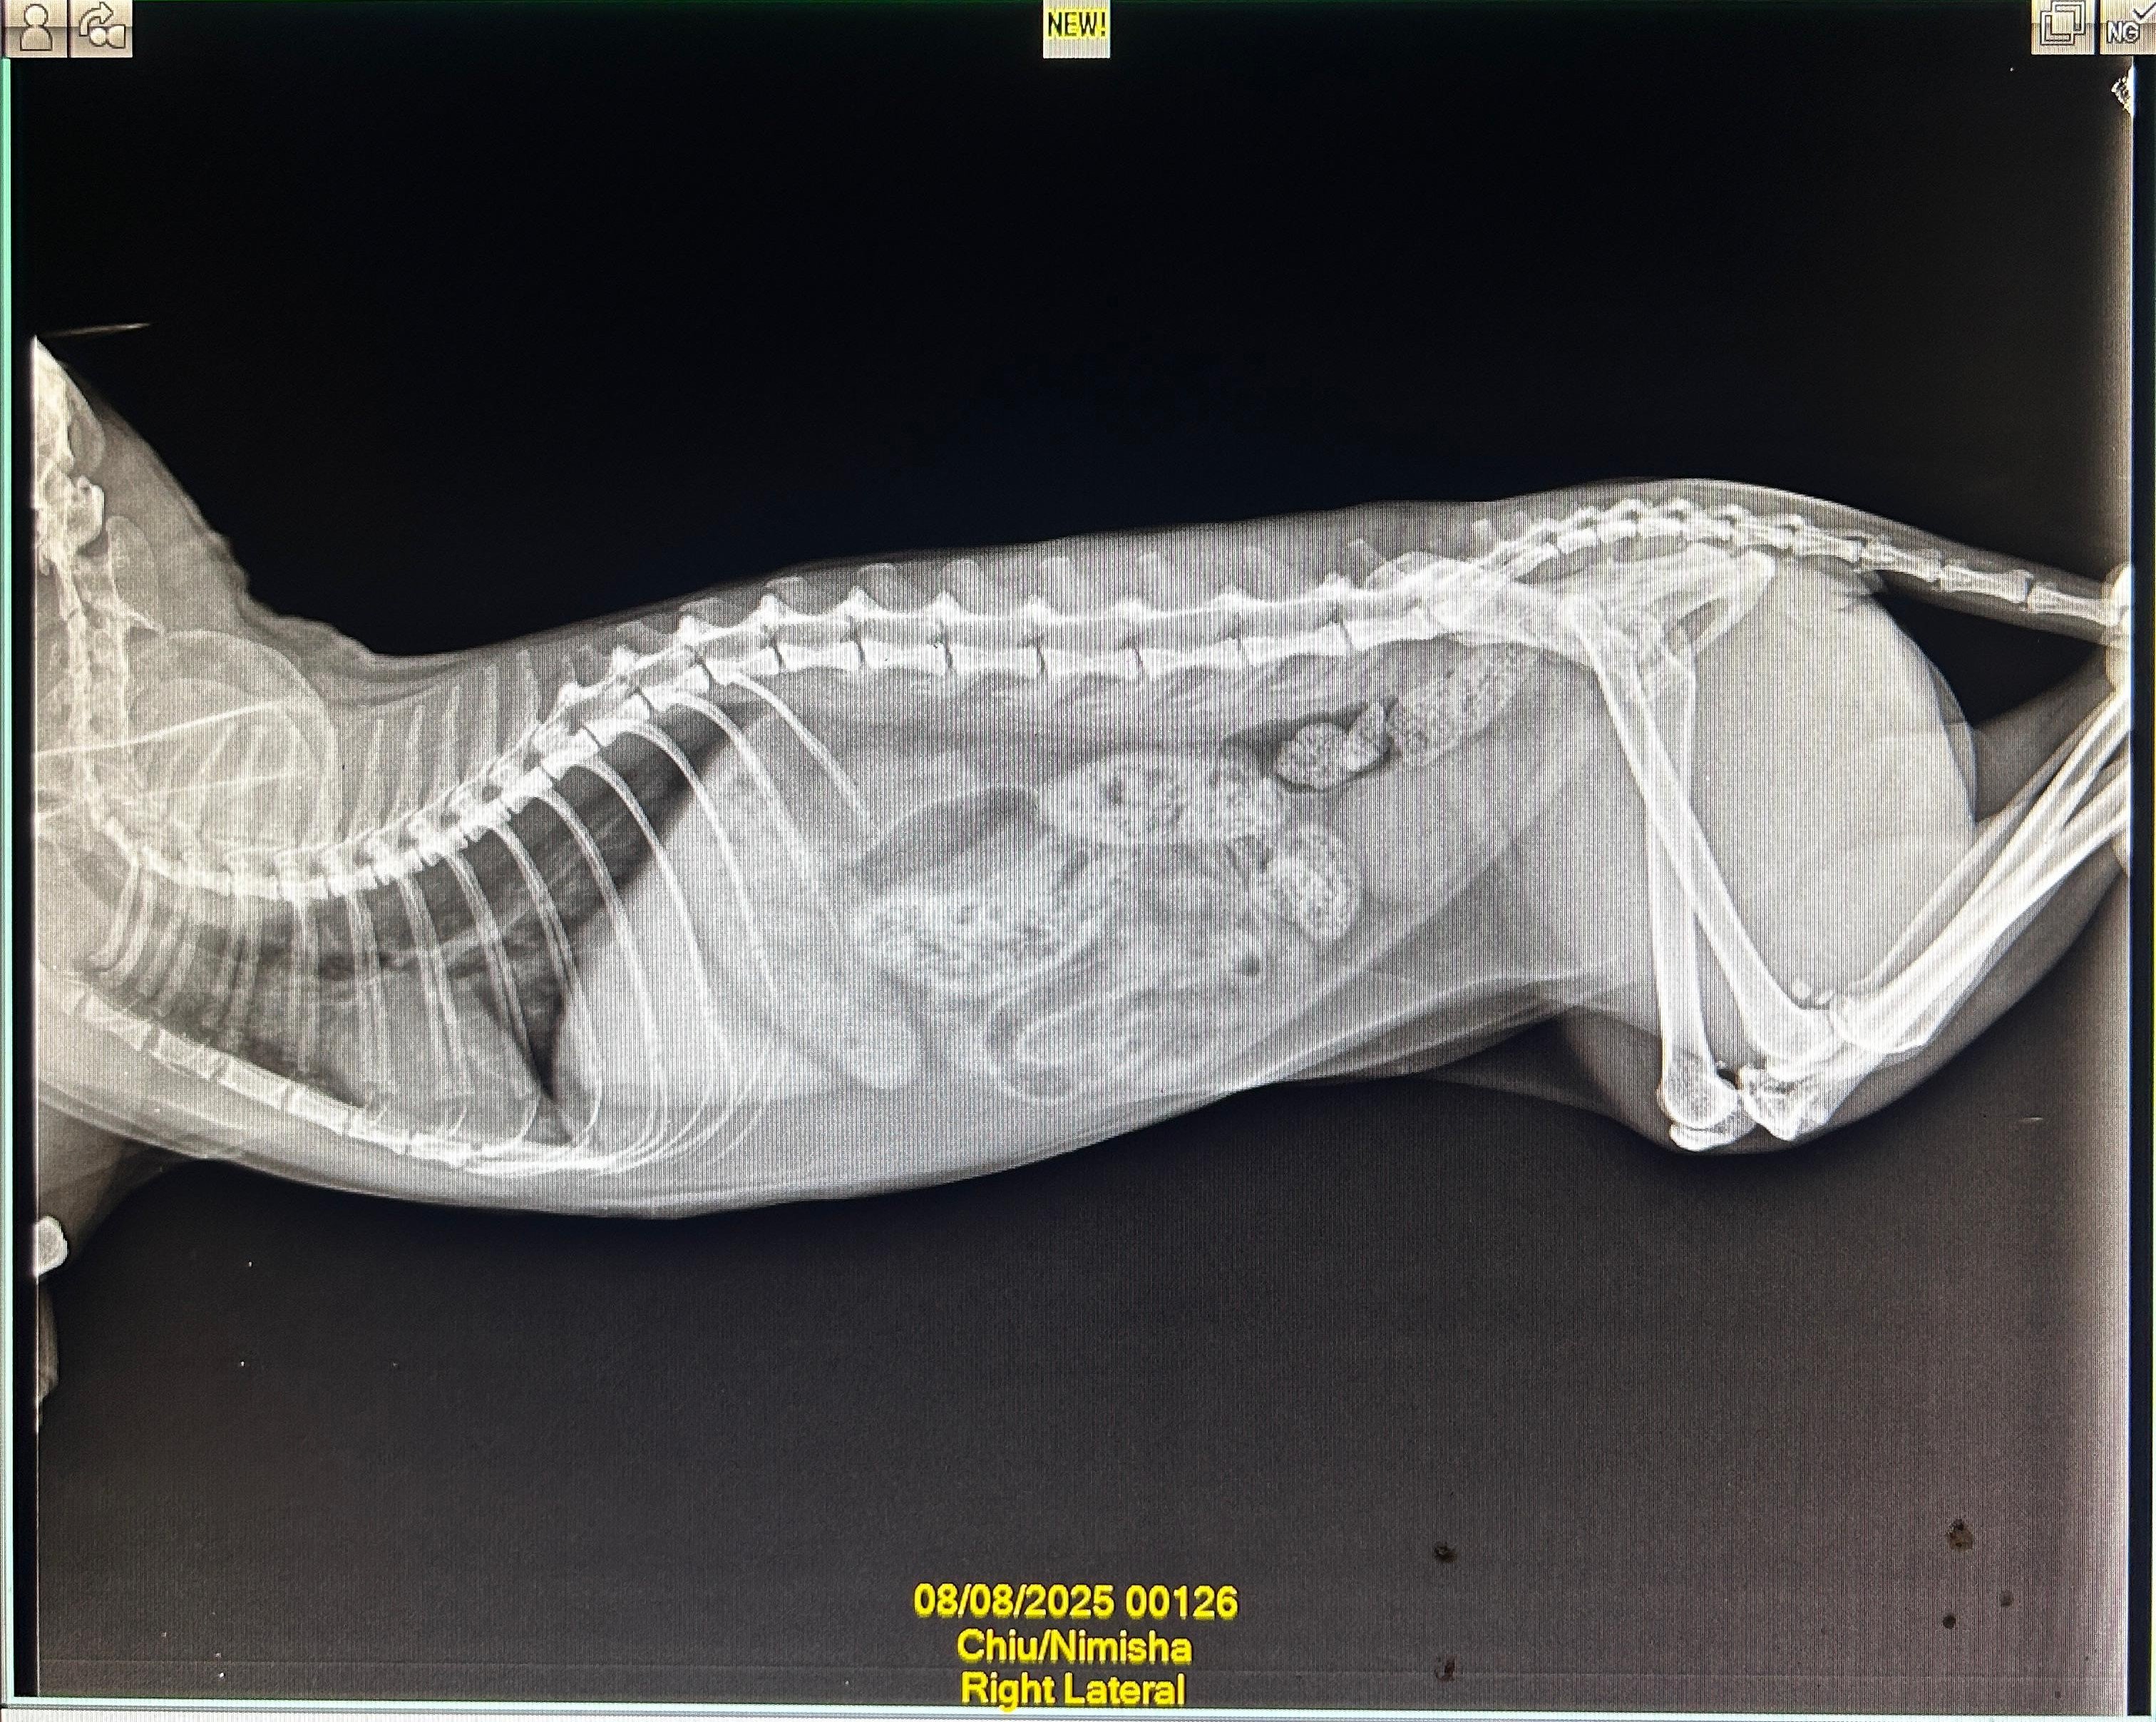

In early August, we got a repeat x-ray (attached) done which still showed bronchial lung pattern. She got Lasix and Penetrat (similar to Frenzyme). She stayed ok for about a month before symptoms returned.

1. Xray - RT LAT - Chiu - 08Aug2025.jpeg1.6 MB · Views: 41 -